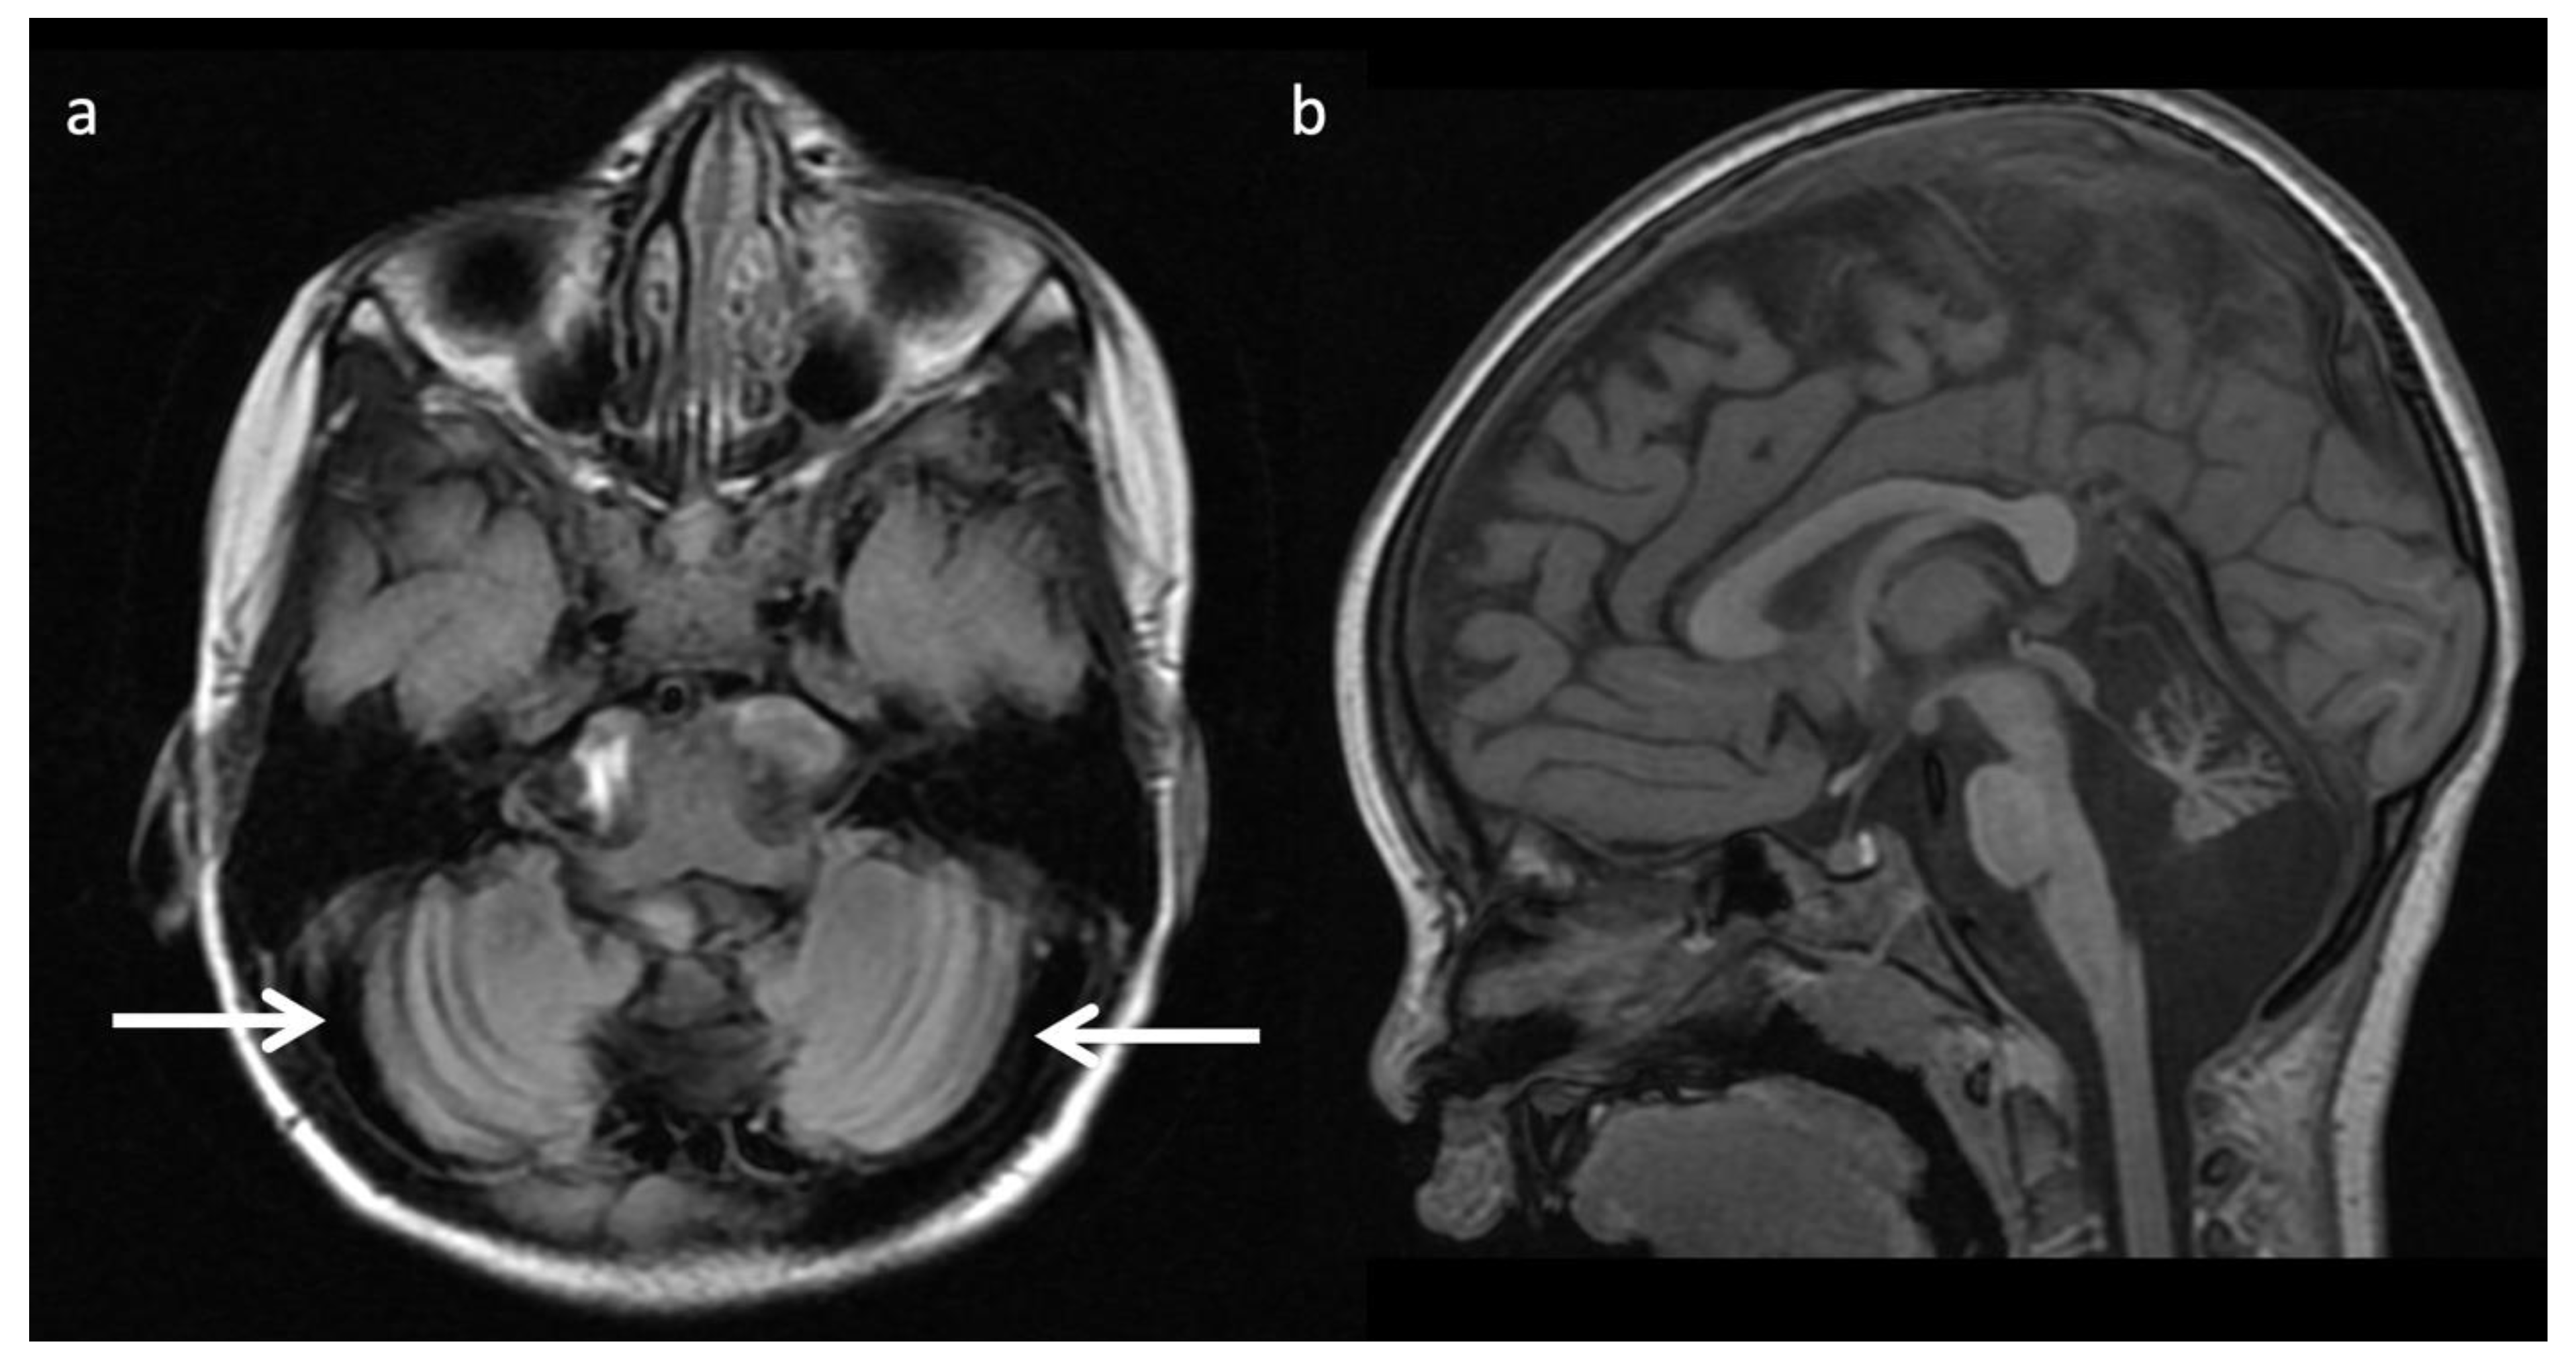

Nonketotic Hyperglycinemia (NKH) or glycine encephalopathy (Figure 9): NKH shows reduced diffusion in myelinated white matter tracts due to intramyelinic edema and vacuolization (usually involving the internal capsules, brainstem, and cerebellar white matter), with extent of involvement less prominent compared to MSUD [3,4,7,8,9]. Additional findings usually include hypogenesis of the corpus callosum and hypoplasia of the cerebellar vermis [7]. MRS reveals an elevated glycine peak at 3.55 ppm, which is best distinguished from the normal mI peak with intermediate or long echo 1H MRS due to its longer T2 decay [3,7,8].

Figure 9.

Two-week-old with seizure activity found to have nonketotic hyperglycinemia (NKH). (a) Axial T2WI at the level of the basal ganglia shows lack of normal myelination related hypointensity in the posterior limbs of the internal capsules. (b) SV-MRS over the left basal ganglia reveals a large glycine (gly) peak at 3.55 ppm (confirmed on longer TE MRS, not shown), mild Lac, mildly reduced NAA and Cho, and possible beta hydroxybutyrate (βHB) from ketosis at 1.18 ppm.